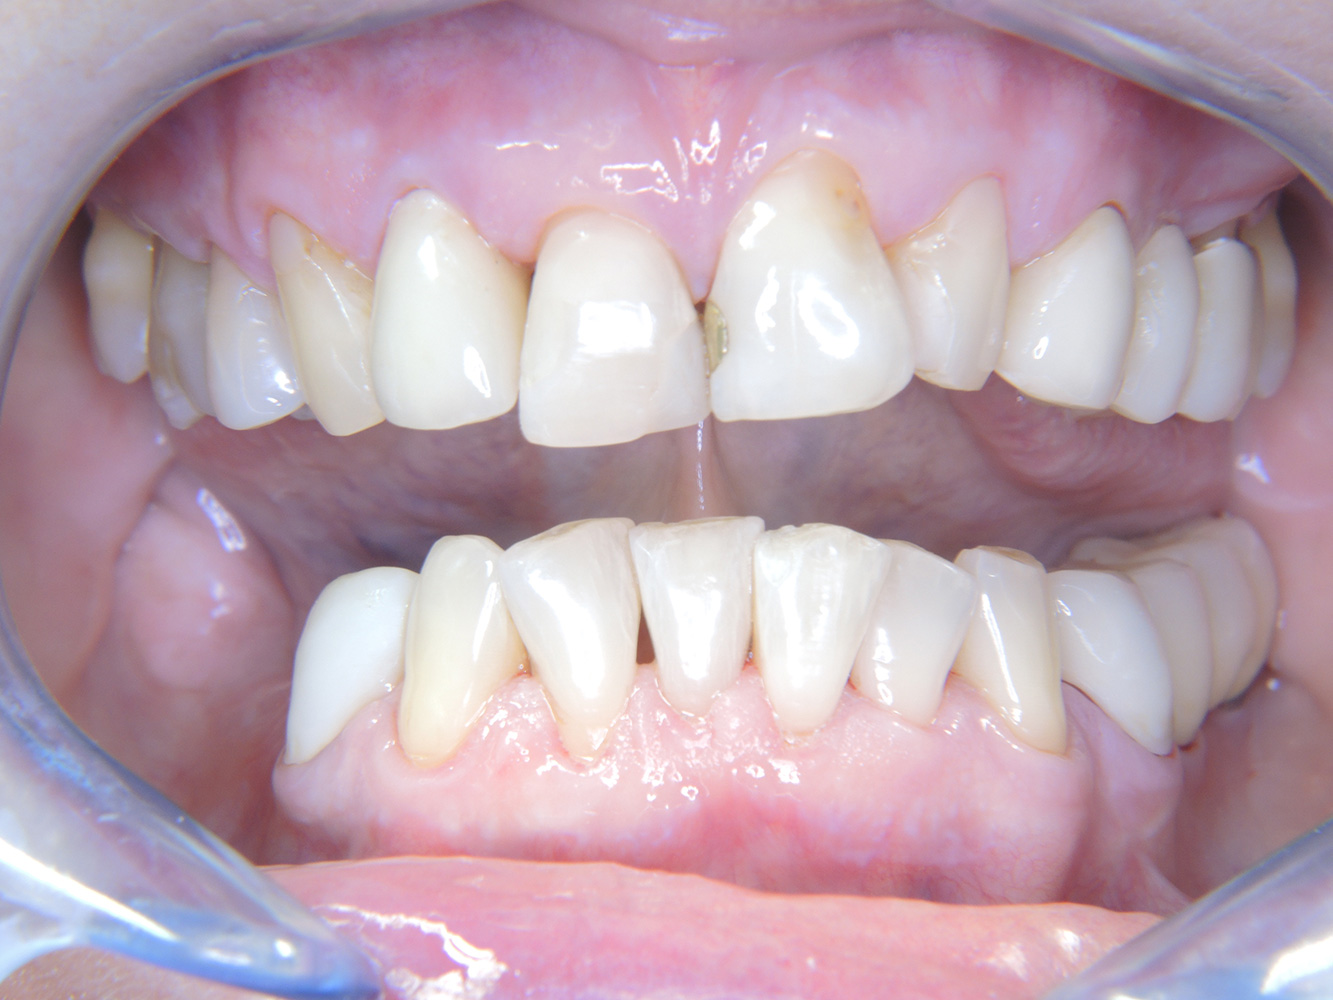

Debido a la situación del implante con la enfermedad periodontal previa, la paciente tiene riesgo de desarrollar periimplantitis; se recomienda un intervalo de recuperación de tres a cuatro meses.